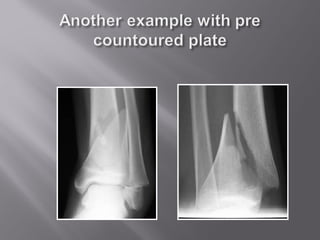

If Injured, Repair the Fibula

Pre-size and bend plate

Or use precountoured plate